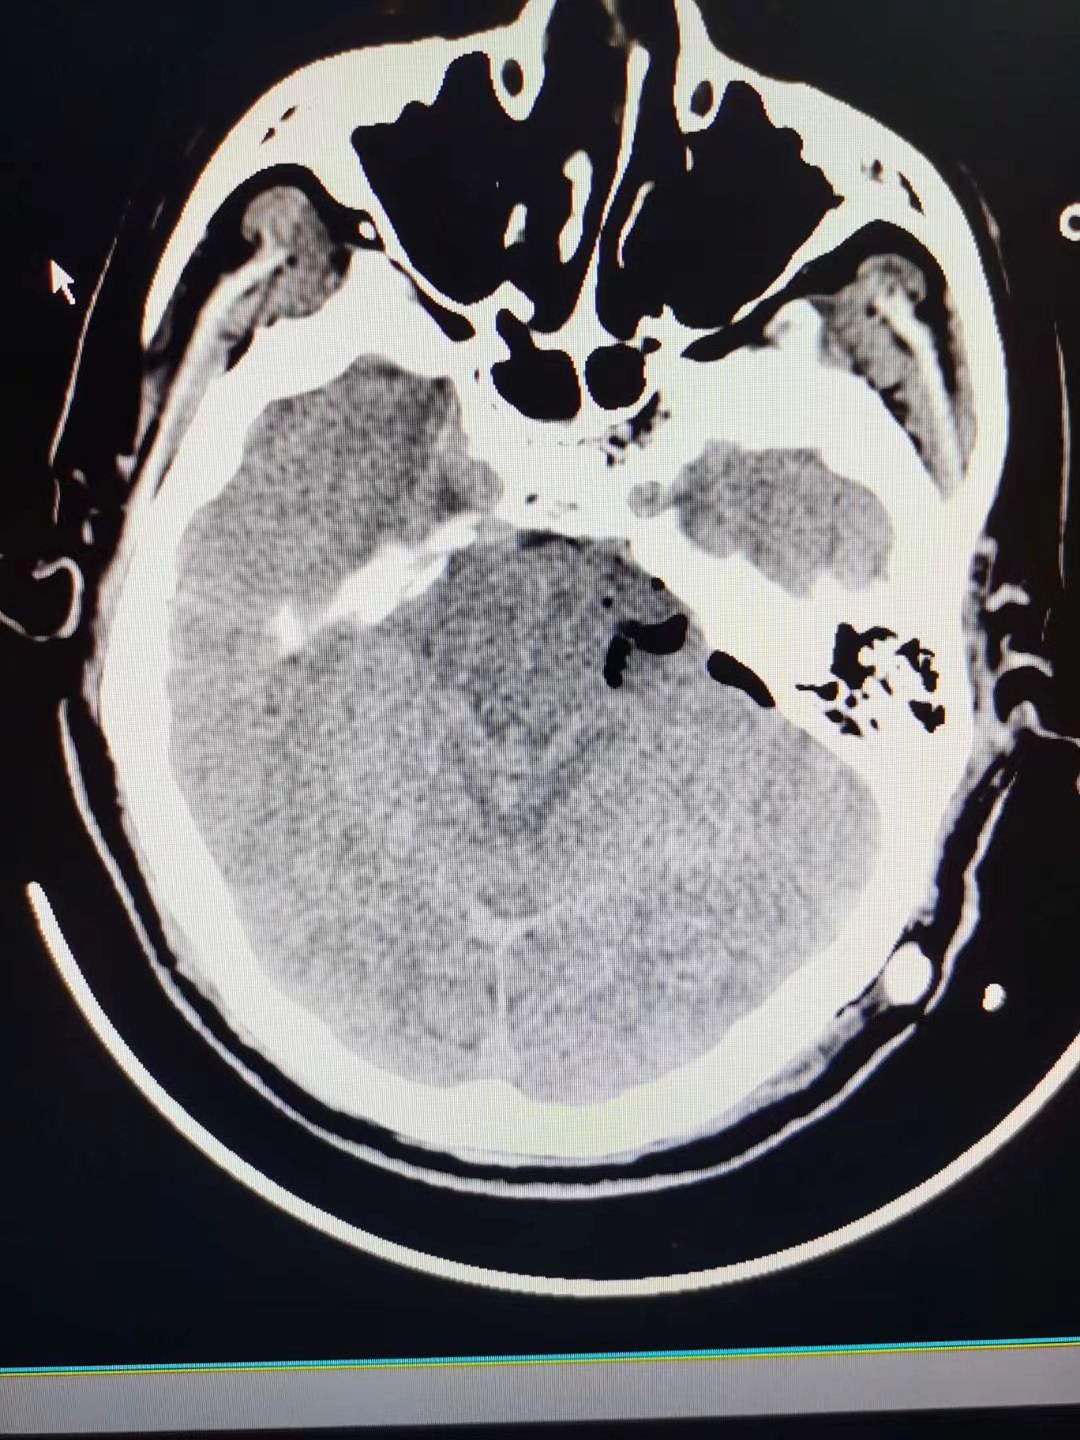

听神经瘤1例

肿瘤全切,术后面神经功能保留完好